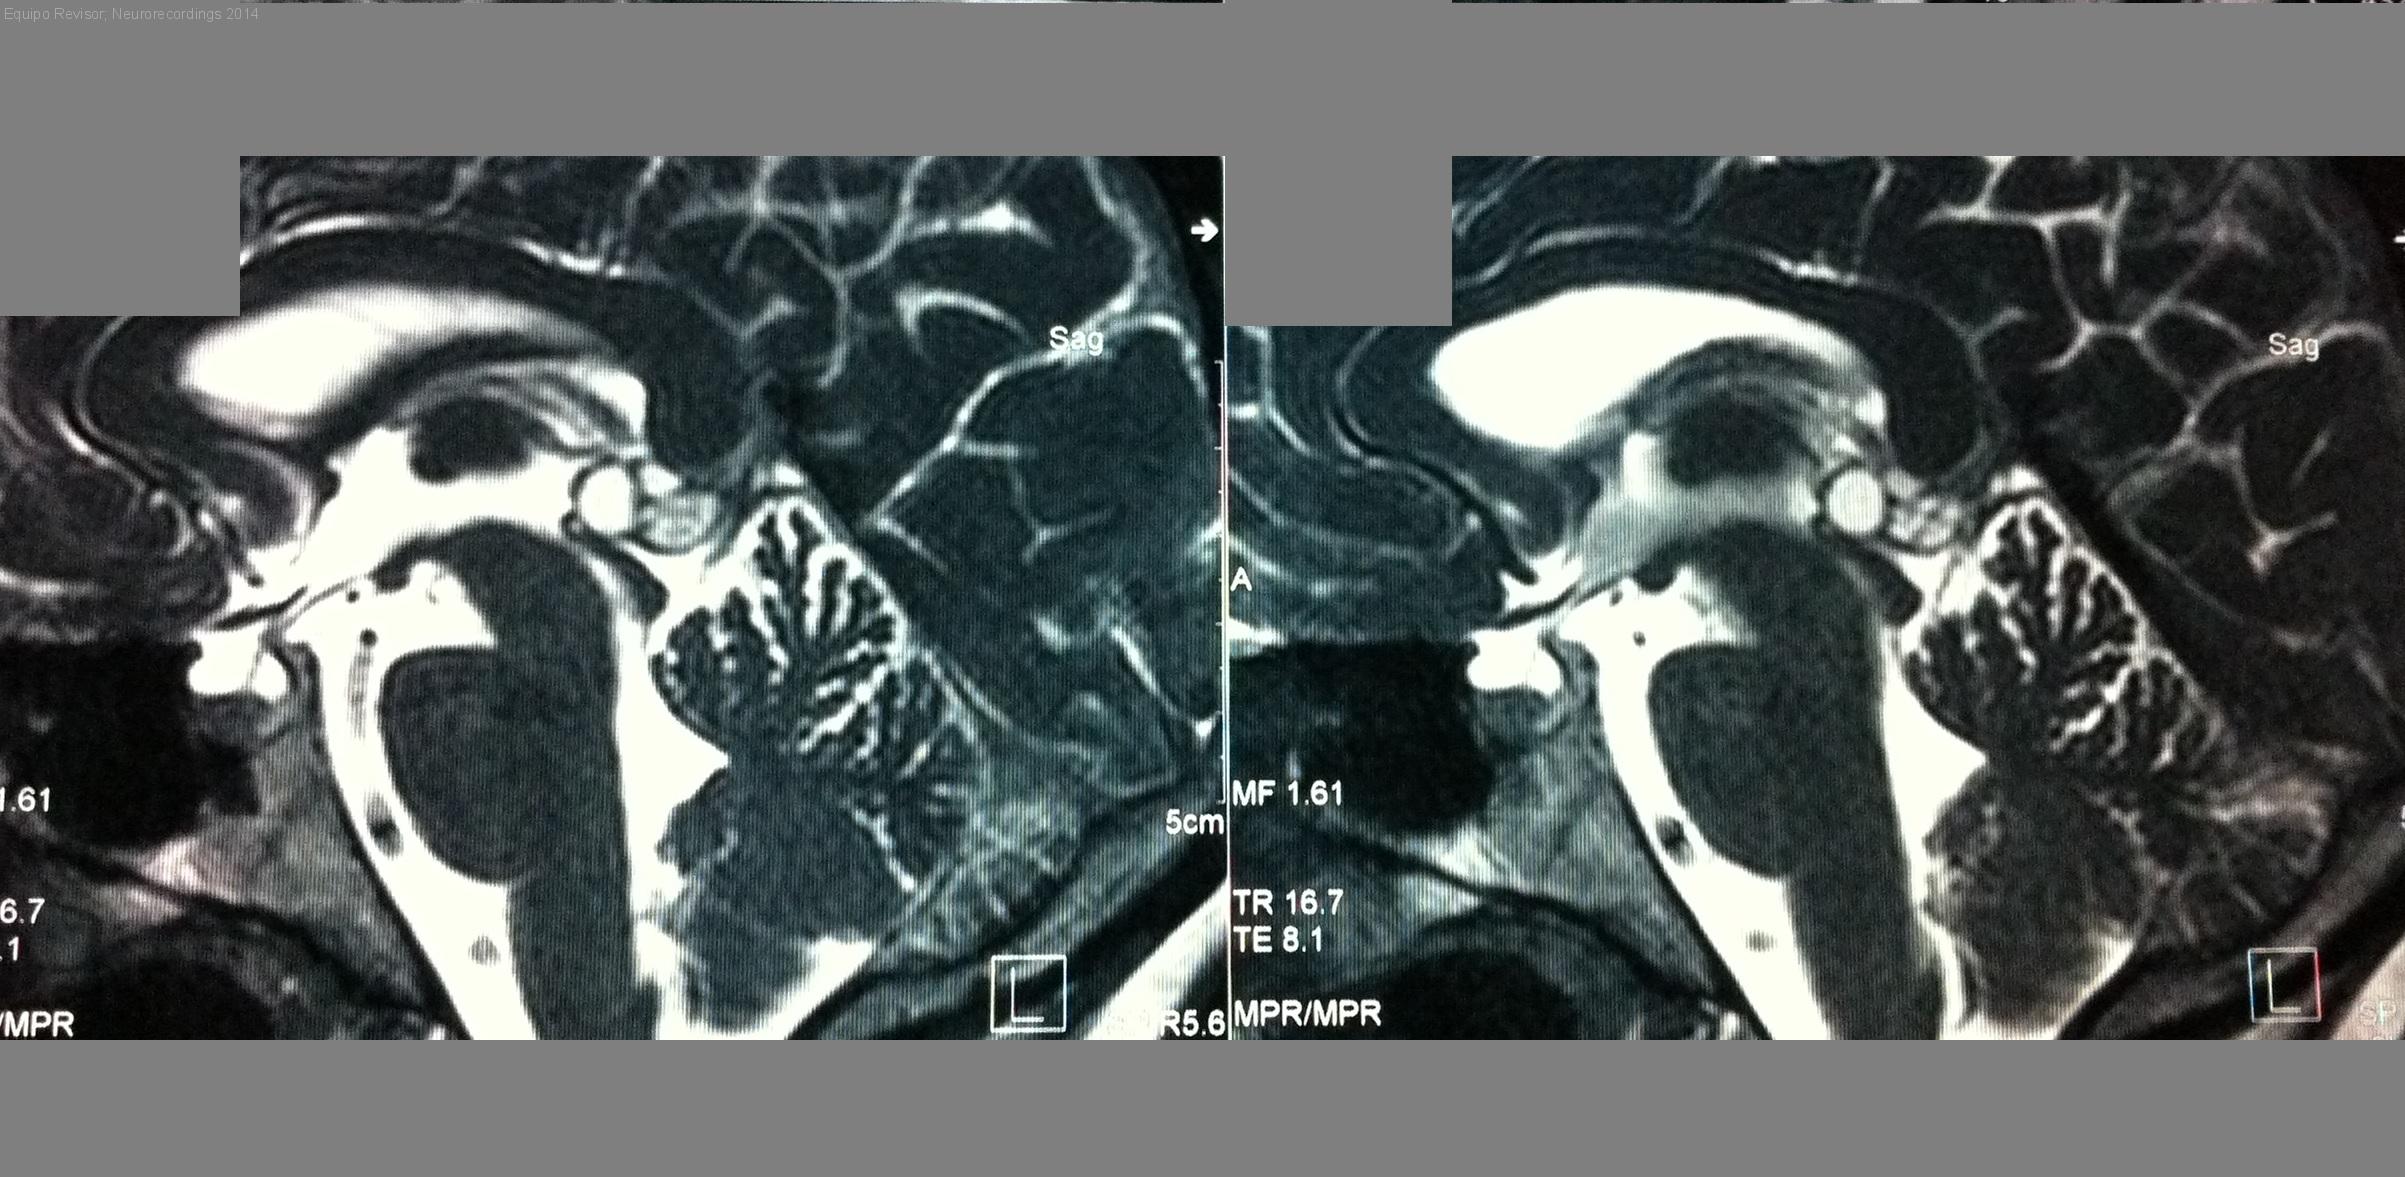

Quiste pineal

Mujer | 26 años

Diagnóstico final: Quiste pineal

Neurología: Anatomía. Variantes de la normalidad

Etiología: Anatomía. Variantes de la normalidad